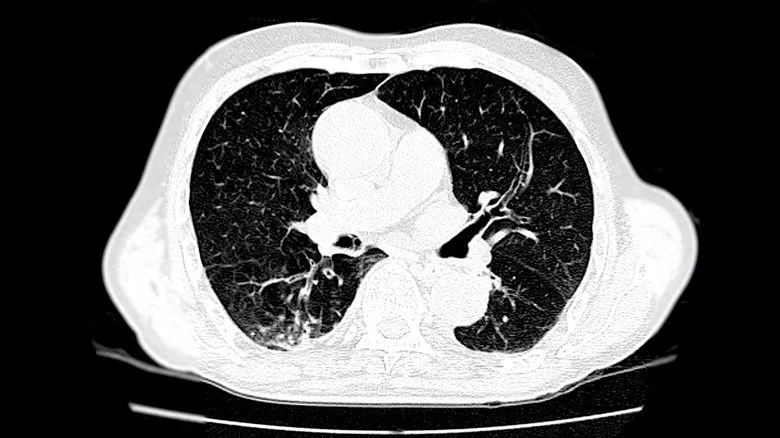

Dog a été un gros fumeur pendant une grande partie de sa vie, mais il a seulement admis l’étendue de son addiction lors de l’émission. Il a révélé qu’il avait commencé à fumer dès l’âge de 12 ans et que pendant plus de 40 ans, il consommait environ trois paquets et demi de cigarettes par jour. Bien que les tests aient étonnamment montré que son cœur était en bonne santé, un scanner de ses poumons a révélé la présence d’un embolie pulmonaire, une condition potentiellement fatale.

Comme l’a expliqué le Dr Oz, une embolie pulmonaire, qui ressemblait à une simple tache sur les images de scan, est un caillot sanguin qui se forme dans l’artère pulmonaire reliant le cœur aux poumons. Ces caillots se forment généralement dans les jambes, dans des veines profondes, et sont transportés jusqu’au cœur puis dans l’artère pulmonaire, où ils peuvent créer un blocage, empêchant le sang de pénétrer efficacement dans les poumons.

Les embolies pulmonaires peuvent être potentiellement mortelles. En bloquant l’artère pulmonaire, elles empêchent le sang d’atteindre les poumons pour être réoxygéné. En plus de détruire les tissus pulmonaires, ces embolies peuvent provoquer une hypertension pulmonaire, un épanchement pleural, une arythmie cardiaque et, dans les cas graves, un arrêt cardiaque. Lors de sa découverte, le Dr Oz a décrit Duane Chapman, grand fumeur, comme une « bombe à retardement, » son addiction aux cigarettes pouvant aggraver les dommages à ses poumons. Le médecin a conseillé au célèbre chasseur de primes d’arrêter définitivement de fumer (via People).

Avant de consulter un médecin, Duane « Dog » Chapman pensait être en bonne santé, car il continuait à faire de l’exercice régulièrement. Cependant, il devint évident sur le plateau du « Dr. Oz Show » que des décennies de tabagisme avaient considérablement affecté ses poumons. Fumer provoque le rétrécissement des vaisseaux sanguins, comme les artères pulmonaires, augmentant ainsi le risque de formation de caillots sanguins et de blocages potentiellement mortels. L’embolie pulmonaire de Dog, qui était la cause de son essoufflement, pouvait s’aggraver avec la poursuite du tabagisme, ce qui pourrait entraîner une crise cardiaque potentiellement fatale.